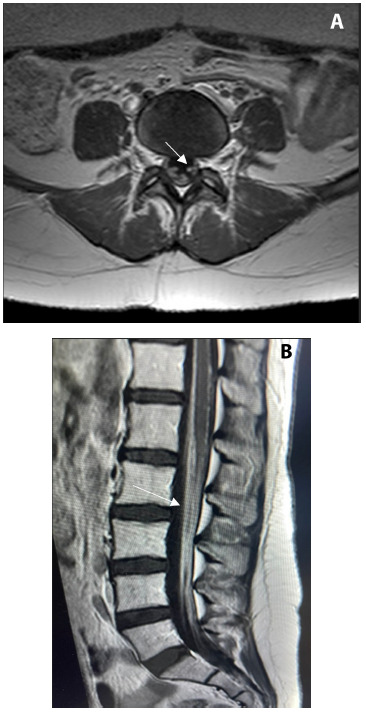

Brucellosis is a zoonotic infection that affects 500,000 individuals each year worldwide. Neurological complications occur in up to 5% of cases, and ocular involvement is rare. This report describes the case of a 26-year-old woman with progressive lower limb weakness and significant ambulatory impairment following two months of headache, nausea, vomiting, and visual disturbances. The patient had a history of urinary incontinence, lower back pain, and raw goat milk consumption. Clinical examination revealed bilateral papilledema and muscle weakness. Positive Brucella culture, abnormalities in the cerebrospinal fluid, and magnetic resonance imaging findings confirmed the presence of neurobrucellosis. Treatment with antibiotics led to minimal initial improvement. However, significant recovery was observed five months post treatment initiation. This case highlights the importance of considering neurobrucellosis in endemic regions and underscores its distinct clinical and radiological features. Early recognition and treatment are crucial for reducing morbidity.